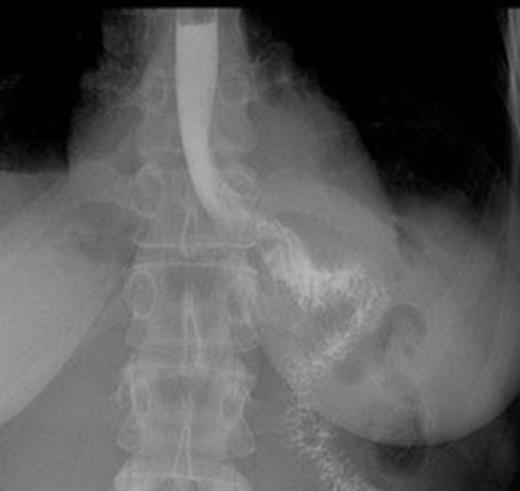

Postoperative contrast swallow

The whole stomach wall was submitted for histological microscopic examination in 67 blocks. No evidence of dysplasia or early foci of signet ring cell carcinoma were seen. The resected lymph nodes were unremarkable. The patient’s postoperative course was uncomplicated with return of bowel function on day 6 and discharge home on day 11. A postoperative contrast swallow was normal on postoperative day 3 (Figure 1). She remains well 5 months following surgery, with satisfactory wound healing (Figure 2).